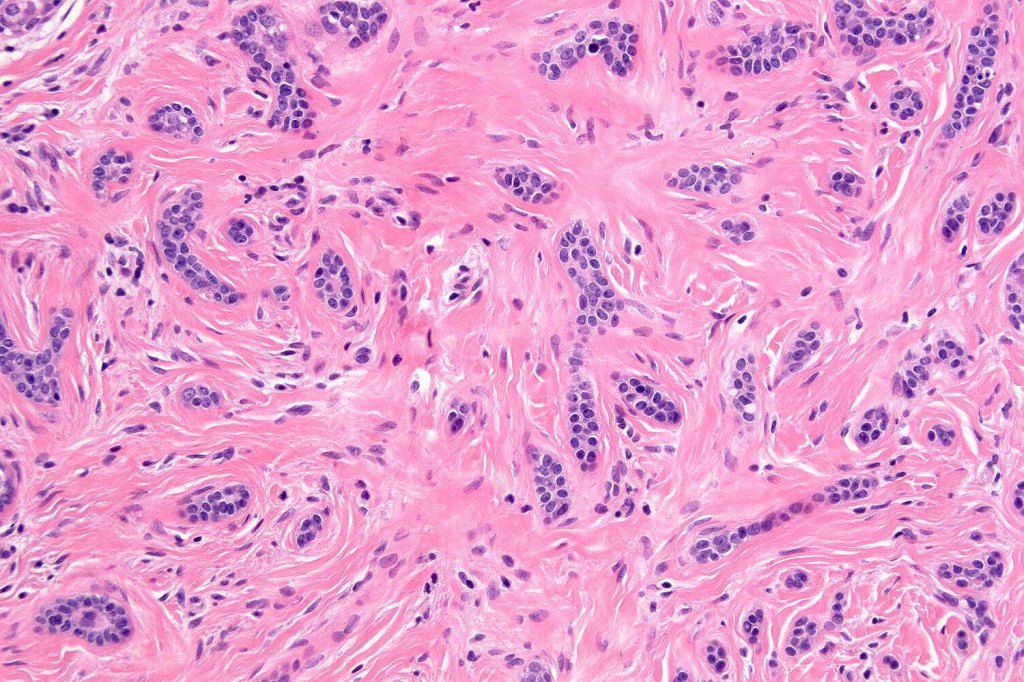

•Consists of narrow epithelial strands & keratocysts embedded in a dense stroma

•No evidence of glandular differentiation

•Epithelial stands may arise from follicular epithelium

. EMA & CEA show no evidence of ductal differentiation